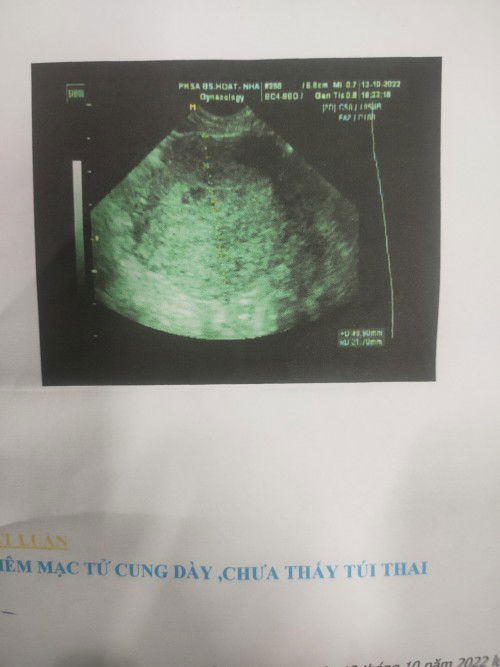

Có mom nào bị trường hợp như vậy chưa ạ . Trước chu kỳ khoảng 7-5 ngày ngực mình đau qua nên thử que thử thì 3 que cách ngày 1 v đậm 1 vạch mờ , minh đi s.a thử bs bảo có thai( hình như co yoksac) nhưng chưa thấy rõ túi mình từng bị sảy nên bs bảo ko dc di lại qa nhiều rồi cho thuốc đặt về đặt hẹn 10bgay tái khám nay chưa tới ngày hẹn nhưng đã trễ 2 ngày mình có thử que thử thì co 1 v vậy co sao ko m.n , ngực mình vẫn còn đau Co ai giống e thai bình thường ko ạ , hay để thêm 1 tuần nữa thữ lại ạ ,e ko bị đau bụng nhiều hay ra huyết gì cả , chỉ lau lau đau bụng dưới lâm râm như kim châm

E có kinh ngày 17/9nay ngày 12/10chưa tới ngày mà ngực đau quá nên thử Thữ que 2 ngày 3 que v

V là có ko ạ m.n